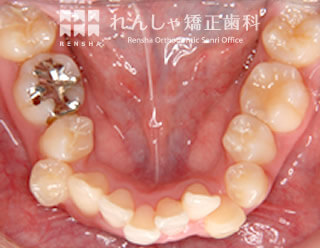

過蓋咬合(14歳 治療期間:2年8か月)

正中離開(前歯の間にあいた隙間)が気になり来院されましたが、過蓋咬合(深い噛み合わせ)が主な原因になっていることがあきらかでした。

下歯列形態は左右非対称になり、右奥歯の噛み合わせがすれ違っています(鋏状咬合)。この噛み合わせを放置すると、上前歯の前突やすきっ歯はさらに悪化し、右奥歯は全く噛めなくなってしまいます。

まず過蓋咬合と右奥歯の噛み合わせを改善し、その後上前歯を後退させました。

| 主訴 | 前歯の隙間と歯ぎしり |

|---|---|

| 診断名 | Angle Class II 過蓋咬合を伴う上顎前突 |

| 初診時年齢 | 14歳5か月 |

| 装置名 | マルチブラケット装置 |

| 抜歯非抜歯 | 上顎両側第一小臼歯(合計2本) |

| 治療期間 | 2年8か月 |

| 費用の目安 | 約89万円+消費税(検査料金、都度の処置費用等も合わせた総額) |

| リスク副作用 | 歯の移動に伴う軽微な歯根吸収、歯槽骨吸収、歯肉退縮(いずれも本症例ではほぼ無し)、矯正器具装着中のカリエスリスク増大(本症例ではカリエス発生無し) |